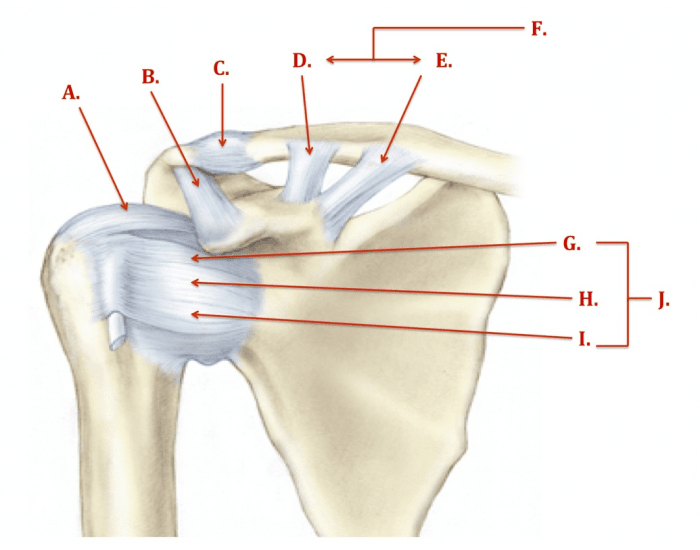

Glenohumeral ligament: анатомия и функции плечевого сустава